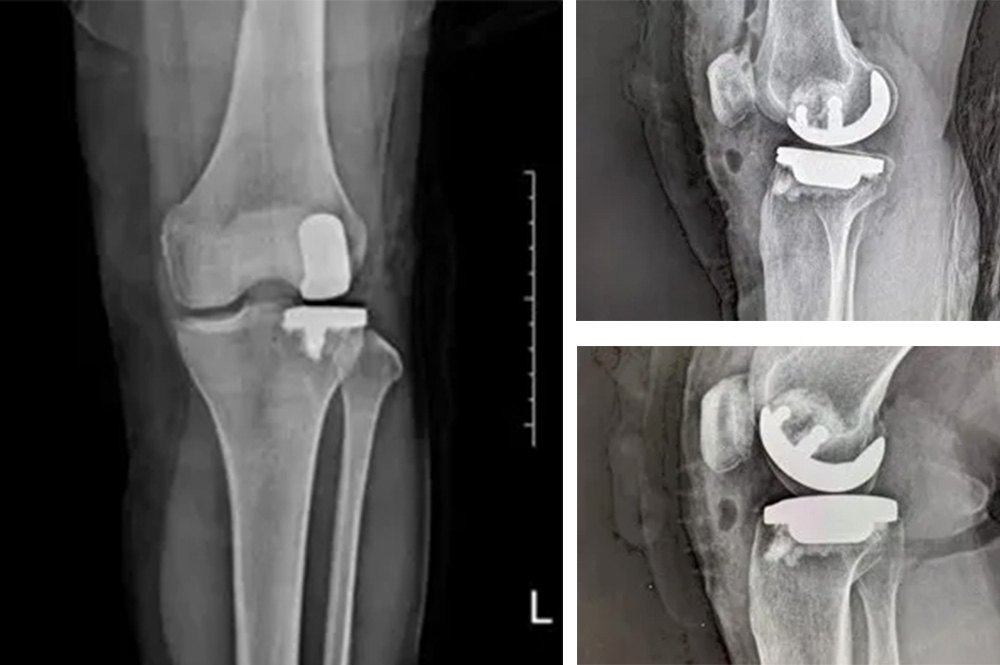

我院骨科主任羅醫(yī)生介紹,膝關(guān)節(jié)分為內(nèi)側(cè)、外側(cè)和髕股三個間室。鮑奶奶的問題主要集中在膝關(guān)節(jié)外側(cè)間室,而內(nèi)側(cè)和髕股關(guān)節(jié)相對完好。

“傳統(tǒng)全膝關(guān)節(jié)置換會切除所有關(guān)節(jié)面,而單髁置換只替換病變的部分,保留了健康的韌帶和軟骨,更符合‘精準(zhǔn)醫(yī)療’理念。”羅醫(yī)生說。

經(jīng)過詳細(xì)的體格檢查、影像學(xué)評估和三維重建,醫(yī)療團(tuán)隊確認(rèn)鮑奶奶的情況非常適合進(jìn)行膝外側(cè)單髁置換術(shù)。這種微創(chuàng)手術(shù)創(chuàng)傷小、恢復(fù)快,能夠最大程度保留膝關(guān)節(jié)的自然結(jié)構(gòu)和功能。

手術(shù)當(dāng)天,骨科團(tuán)隊采用微創(chuàng)切口,僅約8厘米,遠(yuǎn)小于傳統(tǒng)全膝關(guān)節(jié)置換手術(shù)切口。術(shù)中精準(zhǔn)定位,僅置換病變的膝關(guān)節(jié)外側(cè)間室。

手術(shù)使用了最新的單髁假體系統(tǒng),這種假體設(shè)計更符合人體工程學(xué),能夠更好地恢復(fù)膝關(guān)節(jié)的自然運(yùn)動軌跡。

膝外側(cè)單髁置換術(shù)是膝關(guān)節(jié)置換領(lǐng)域的重要進(jìn)展。與全膝關(guān)節(jié)置換相比,它具有明顯優(yōu)勢:手術(shù)創(chuàng)傷小,僅置換病變部分;保留更多自然結(jié)構(gòu)和韌帶;術(shù)后恢復(fù)快,住院時間短;術(shù)后膝關(guān)節(jié)感覺更自然,活動度更好。